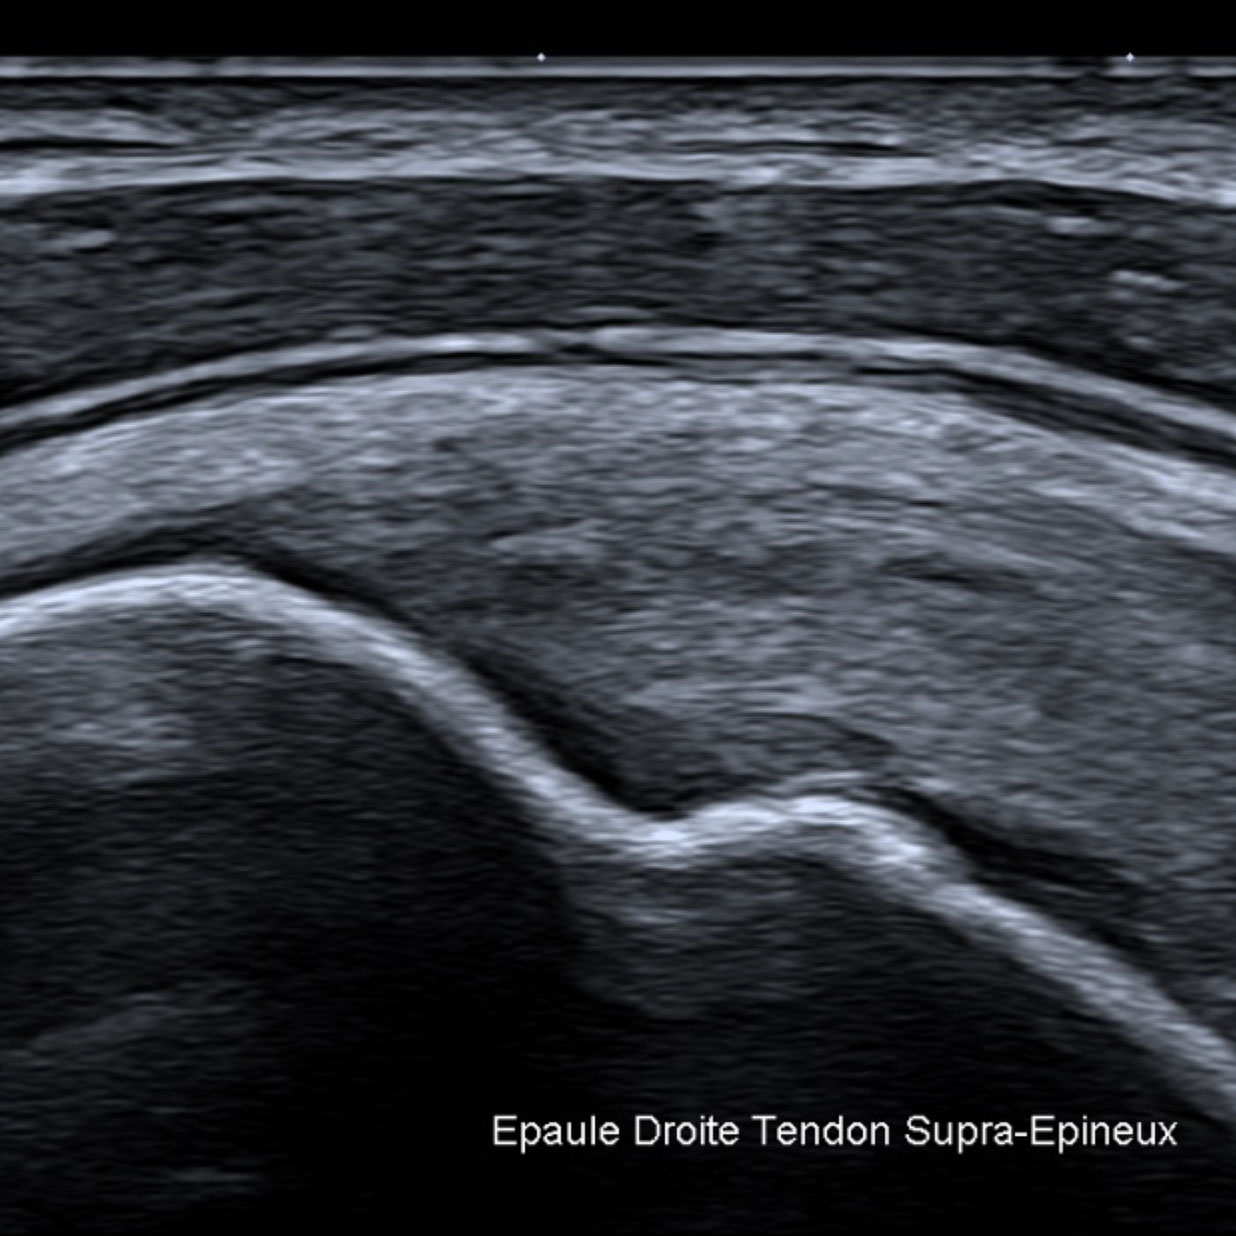

Pour exemples, les liquides purs apparaissent noirs (anéchogène) sur l’écran. Les tissus ou les liquides épais (mucoïde, hématome) apparaissent gris, les calcifications tout comme le gaz et l’air réfléchissent complètement les ultrasons et sont visibles sous la forme d’une ligne blanche sans aucun écho sous-jacent.

Pendant l’examen le médecin réalise plusieurs clichés et les images sélectionnées sont imprimées et jointes au compte rendu. Elles n'ont qu'un rôle d'illustration, la qualité de la reproduction ne permettant en aucun cas de réévaluer, par exemple, un diagnostic.

-Echographie des tendons de la coiffe en mode harmonique : les clivages sont-ils enfin visibles

Guerini H, Feydy A, Campagna R, Thèvenin F, Fermand M, Pessis E, Chevrot A, Drapé JL.

J Radiol. 2008 Mar;89(3 Pt 1):333-8